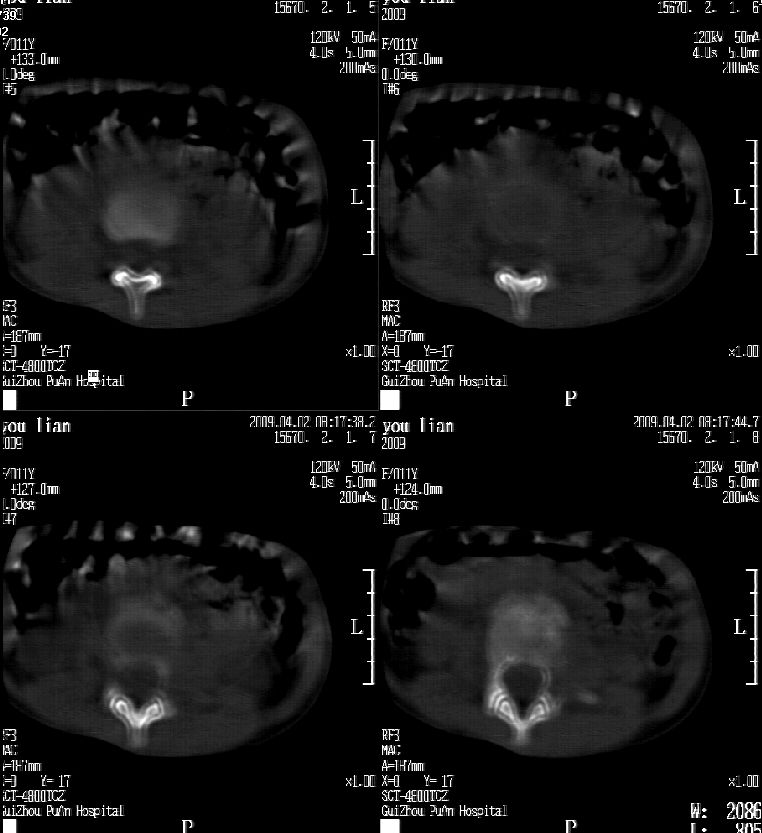

患儿女,11岁,因“腰痛,腰部活动受限10余天”入院。

10余天前,患儿无明诱因出现腰部疼痛,为持续性钝痛,以右侧为著,伴腰部活动受限,有发热,具体体温不详,无寒战、黄疸、盗汗、咳嗽,无尿频、尿急、肉眼血尿。

查:t37.8℃ bp100/60mmhg,心肺腹(-),腰部活动受限,腰椎旁有压痛,双下肢不肿,神经系统检查未见异常。

辅查:血生化未见异常。抗“o” 阳性,类风湿因子阴性,血常规:n79.3%

l 16.9% esr 28mm/h,作腹部b超未见异常,胸片未见异常。

乍一看像是嗜酸性肉芽肿,但看到ct表现骨质破坏及软组织肿胀考虑结核可能性大,鉴别恶性肿瘤.

本例ct图像太不清楚了,而且不知道有没有传完,如果软组织病变只局限性于那几个层面的话多考虑嗜酸性肉芽肿,其次为其他肿瘤,结核椎旁软组织较广泛,在本例没有太典型表现,建议楼主(孩子父母吧)把所有的软组织窗图像(白色的那种)按顺序全部转上来.

考虑l3嗜酸性肉芽肿。